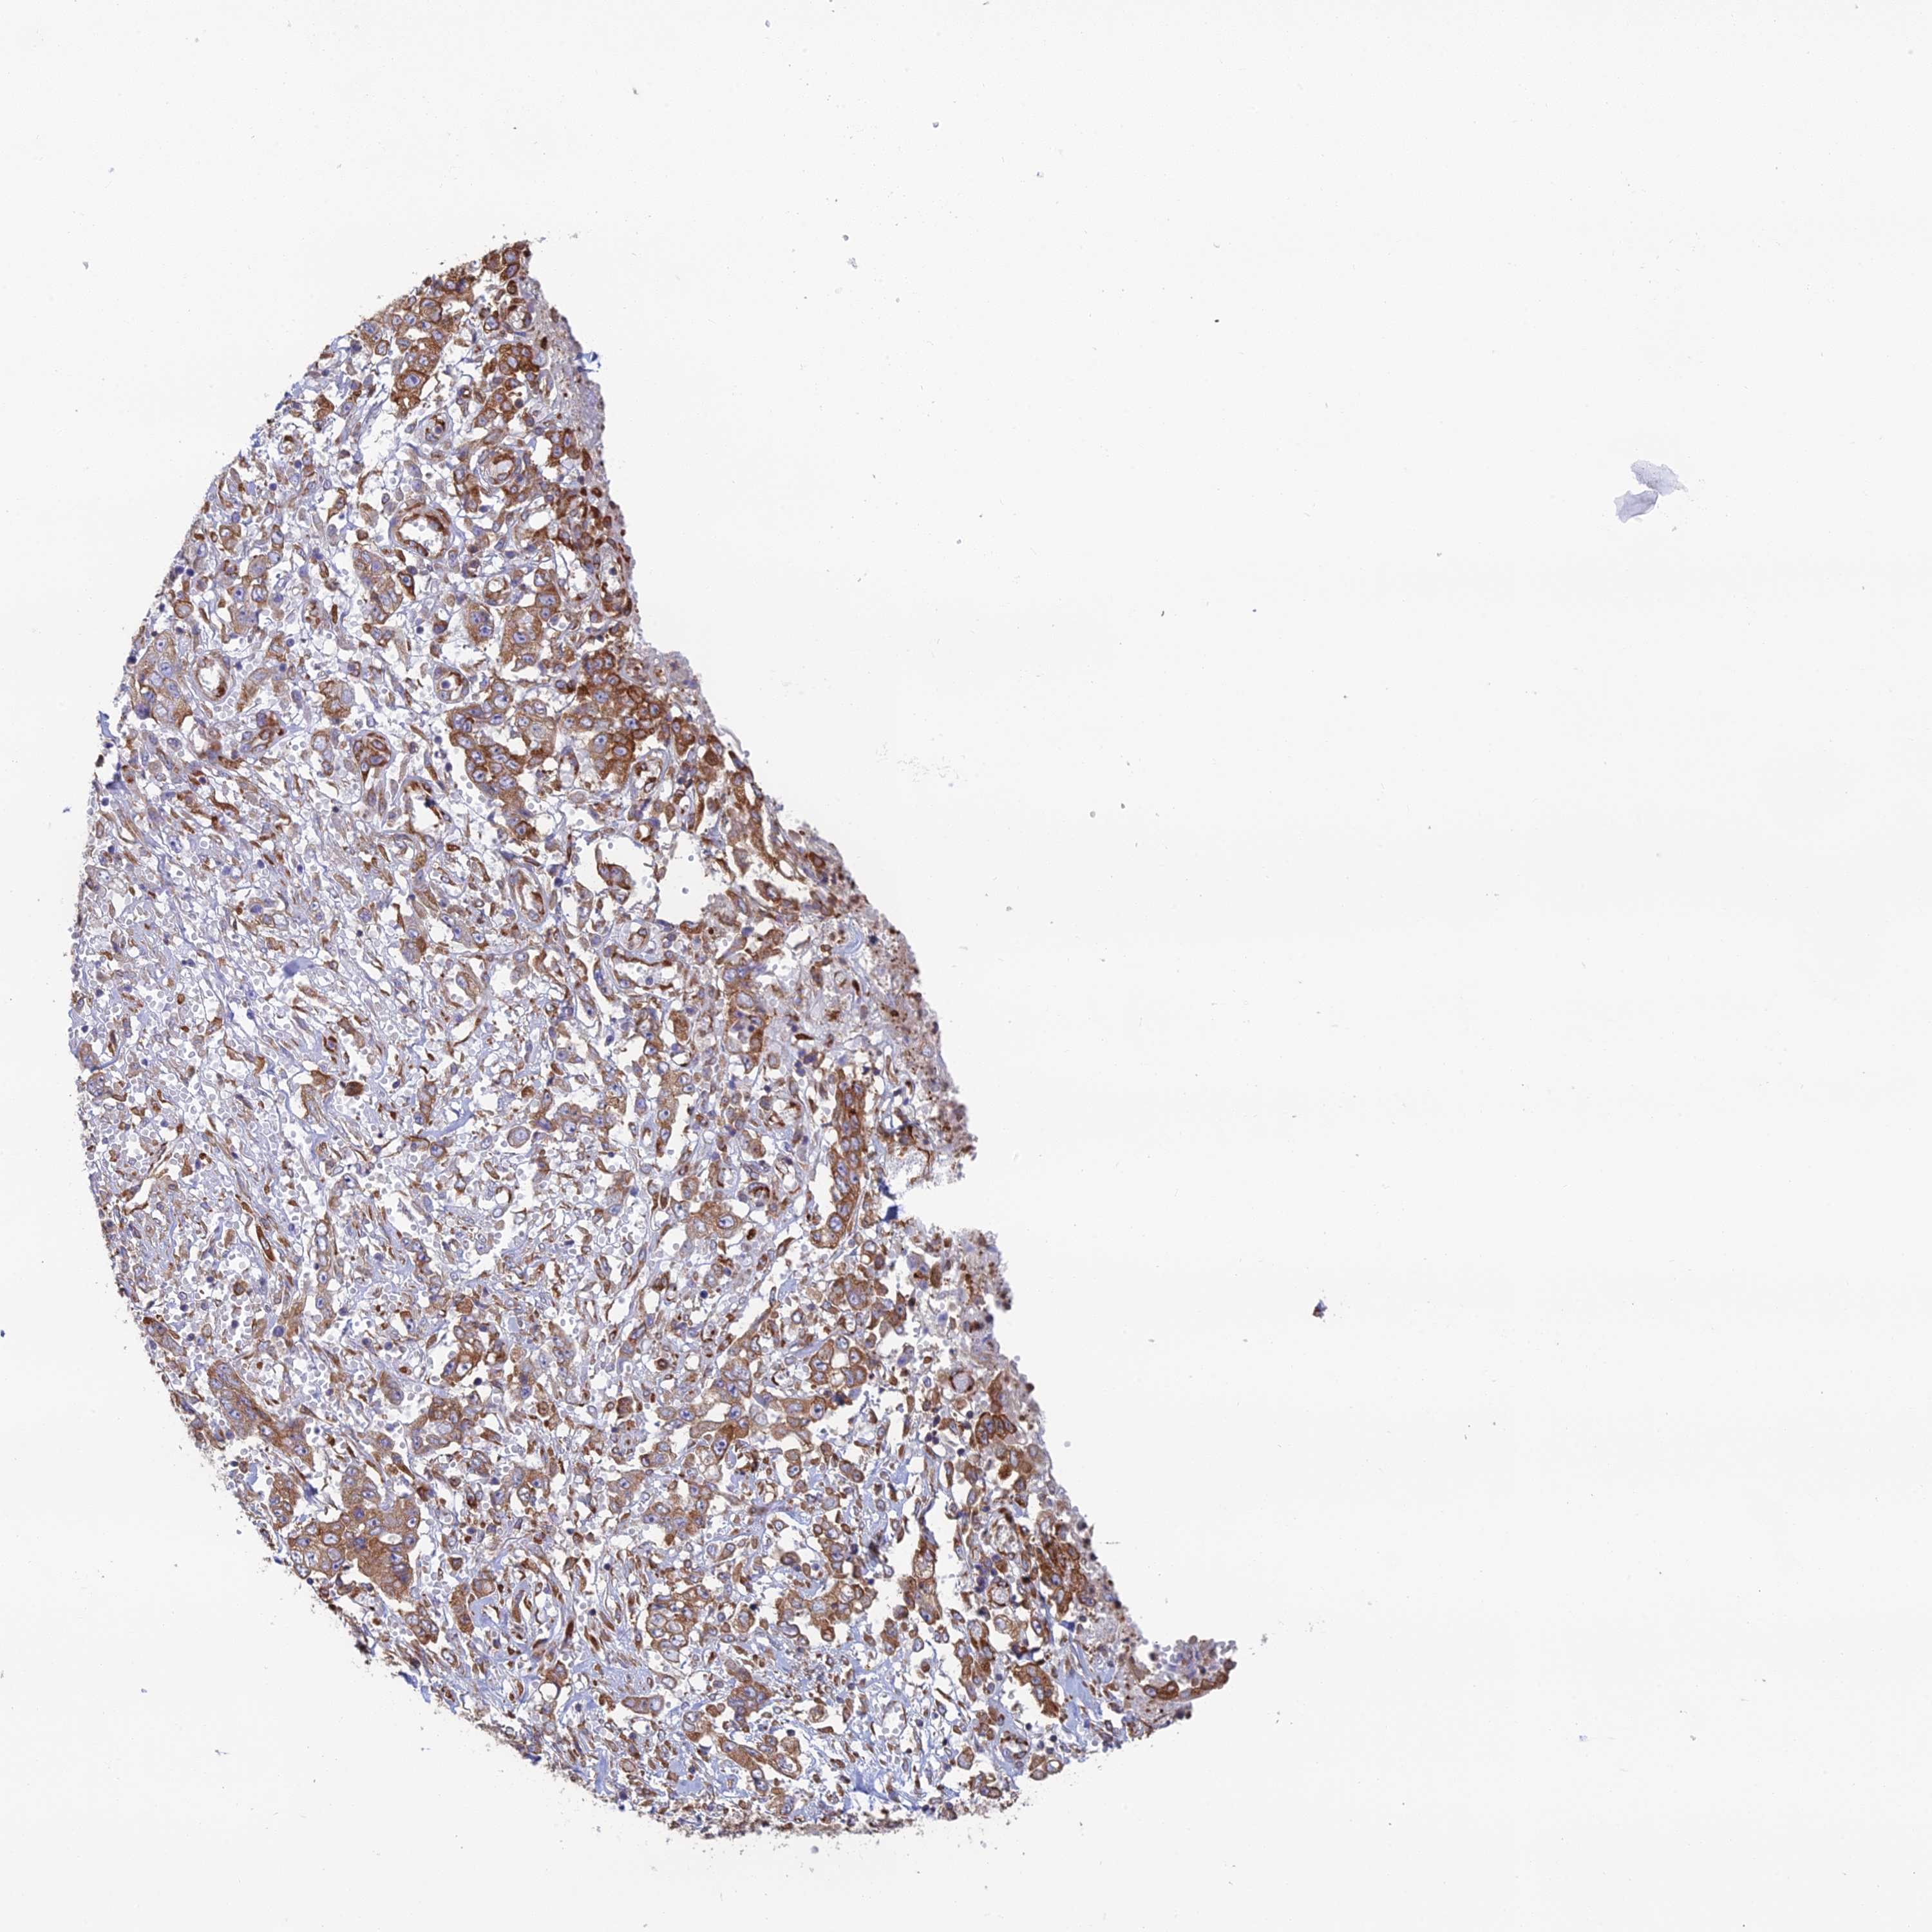

STOMACH CANCER - Protein expressioni

A mouse-over function shows sample information and annotation data. Click on an image to view it in a full screen mode. Samples can be filtered based on level of antibody staining by selecting one or several of the following categories: high, medium, low and not detected. The assay and annotation is described here.

Antibody stainingi

Antibody staining in the annotated cell types in the current human tissue is reported as not detected, low, medium, or high, based on conventional immunohistochemistry profiling in selected tissues. This score is based on the combination of the staining intensity and fraction of stained cells.

Each image is clickable and will lead to virtual microscopy that enables deeper exploration of all samples and also displays staining intensity scores, fraction scores and subcellular localization as well as patient and tissue information for each sample.

Antibody HPA043648

Staining

High

Medium

Low

Not detected

Intensity

Strong

Moderate

Weak

Negative

Quantity

>75%

75%-25%

<25%

None

Location

Nuclear

Cytoplasmic/membranous

Cytoplasmic/membranous,nuclear

Adenocarcinoma, NOS